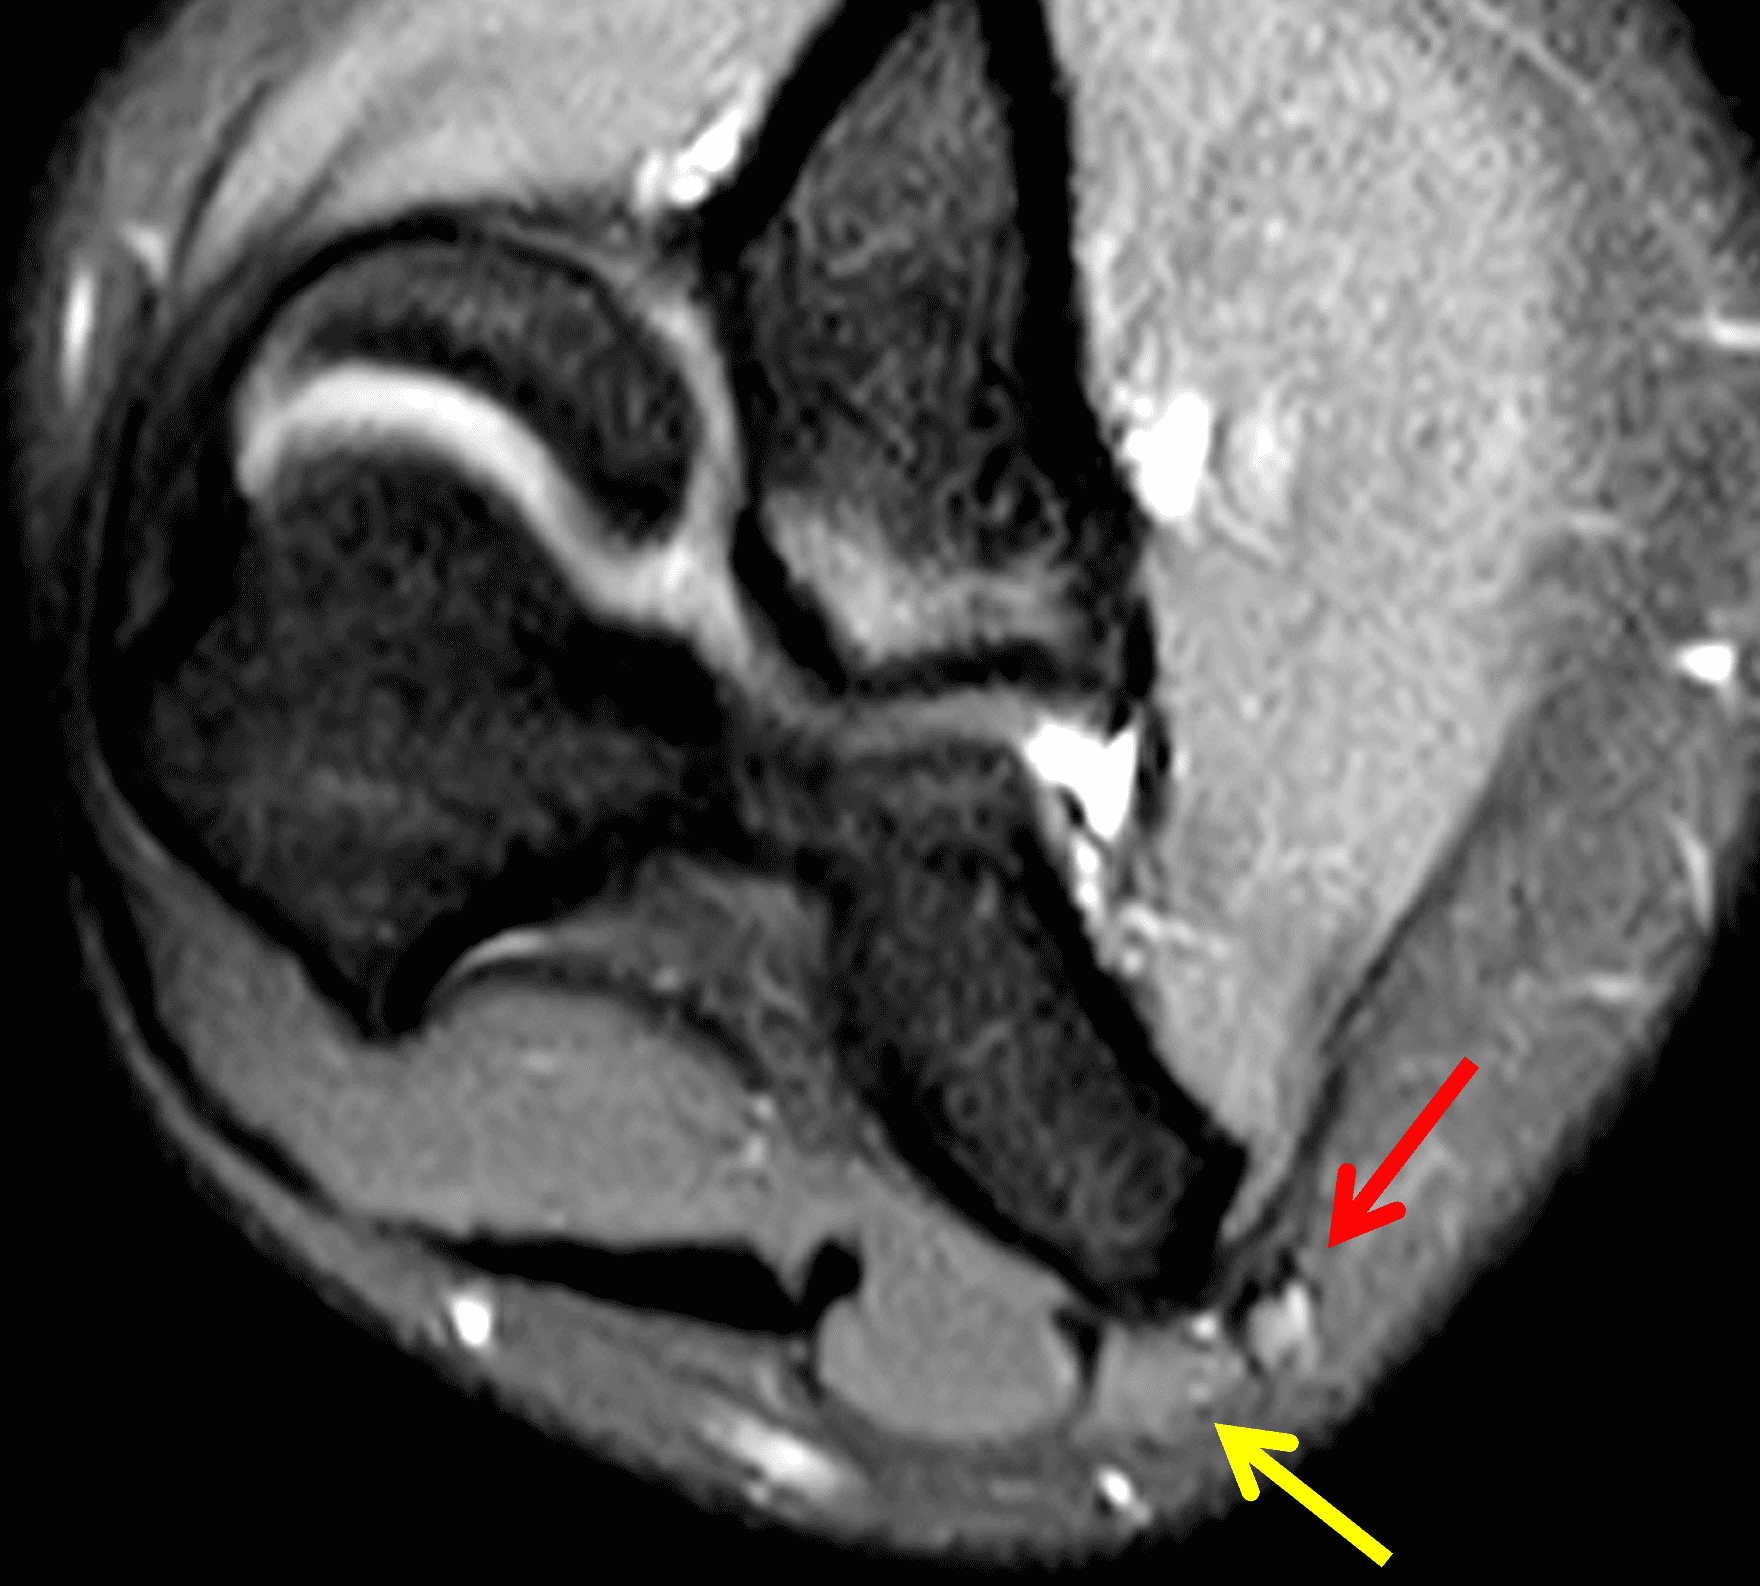

Figure 2: At the level of the cubital tunnel (2A and 2C), identifiable by the thin cubital tunnel retinaculum (yellow arrow), the ulnar nerve (red arrow) is focally enlarged and hyperintense compared to the nerve more distally (2B and 2D), where it lies between the two heads of the flexor carpi ulnaris muscle (asterisks). No soft tissue mass is present.